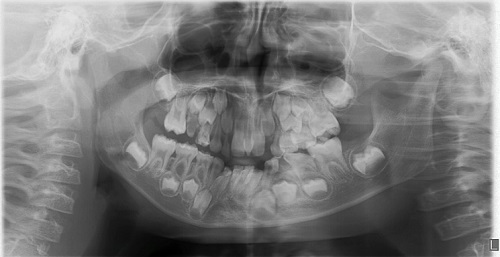

Paciente varón de 10 años, sin antecedentes familiares ni personales de interés, que acude a la consulta de Pediatría por notar un “bulto” en línea media de maxilar superior, por lo que se deriva a la consulta de Odontología. En la exploración dental se observa la presencia de toda la dentición permanente en normoclusión, desgaste selectivo en incisivos inferiores que afecta más a la pieza 32, rotación mesial de la corona del 21 y caries en cara oclusal de 46 (Fig. 4). Se le solicitó una ortopantomografía para valorar el estado de los incisivos. En la radiografía (Fig. 5) vimos la presencia de un mesiodens en la línea media, único, tuberculado y con curvatura apical. El ápice del supernumerario se encuentra próximo al ápice del 21 y altera la correcta alineación de los incisivos inferiores, por lo que presenta desgaste selectivo por oclusión con dicho supernumerario. Además, se aprecia rotación mesial de 21 por la relación con supernumerario y desviación a distal del ápice del 21. Para evitar el daño de incisivos inferiores por prematuridad en oclusión con dicho supernumerario y alteraciones en la posición del 21, se informa a los padres de la necesidad de extraer dicho diente y se realiza en la consulta con anestesia tópica inicial y posterior infiltrativa (Fig. 6).

| Figura 5. Ortopantomografía. Se observa dentición permanente completa, no hay otros supernumerarios ni agenesias. Presenta supernumerario mesiodens en relación apical con 21 formación radicular completa de incisivos centrales y de mesiodens |